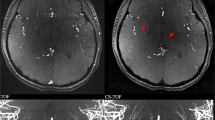

The inter-observer agreement for stenosis assessment was 0.956 (95% confidence interval 0.928, 0.973). Detailed comparisons between CS TOF-MRA and DSA for evaluating intracranial and cervical arterial stenosis are summarized in Table 1 and Supplementary Tables S3. The luminal stenosis ratios measured on CS TOF-MRA were higher than those measured on DSA, but significant differences were only found in mild stenosis (Supplementary Table S3). The luminal stenosis grade of CS TOF-MRA was concordant with that of DSA in 50 of 61 segments (82.0%, Table 1). No significant differences between the luminal stenosis grades assessed on CS TOF-MRA and DSA were found according to the Wilcoxon signed-rank test (p = 0.366). Of the remaining 11 segments, 7 segments were overestimated and 4 segments were underestimated. Detailed results of those segments are summarized in Table 2. A representative case is shown in Fig. 1. (Several mismatched cases are presented in Supplementary Figures S2 to S5.)

Compressed sensing time-of-flight MR angiography (CS TOF-MRA) and DSA in a 53-year-old patient. CS TOF-MRA shows a focal high-grade stenosis in the proximal M2 segment of the right middle cerebral artery with visible distal branches (a, hollow white arrow), and a focal high-grade stenosis in the proximal internal carotid artery (a, b; white arrow). DSA reveals almost identical features of stenosis (white hollow arrow in c, and white arrow in e) at the corresponding locations. Signal loss along the distal segment of the left vertebral artery is observed in CS TOF-MRA (a, white arrow head). DSA shows a left hypoplastic vertebral artery without any stenosis (d, white arrow head)